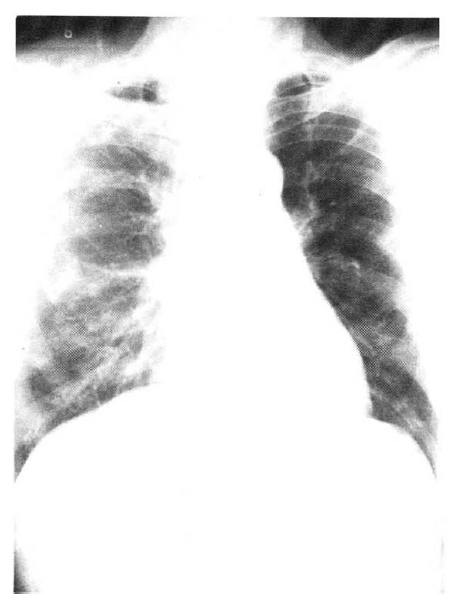

An X-ray film of the chest showed multiple nodular densities throughout both lower lung fields (Fig. 1). A computed tomographic scan of the brain and chest revealed multiple nodular and small calcified densities (Fig. 3, 4).

Afterward, the patient was treated with praziquantel 50 mg/kg/day for 15 days and discharged on the 18 th hospital day, even though he still reported some weakness, cough, and sputum production. One month after discharge, his symptoms began to improve. Six months after treatment, the subcutaneous nodules had decreased to half in size. An X-ray film of the chest revealed nearly normal conditions in the lungs(Fig. 2).